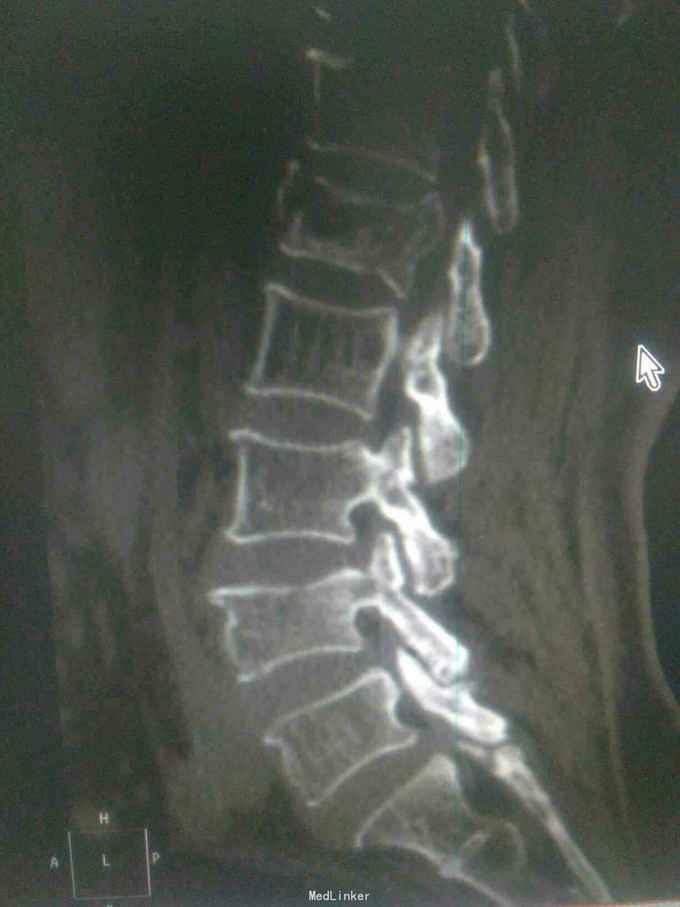

诊断腰1,腰4椎体爆裂性骨折,腰5椎体压缩性骨折,脊髓圆锥损伤双下肢截瘫。患者入院后48小时内行了腰椎后路腰1.4椎体切开复位椎弓根钉内固定,腰1椎板切除,椎管扩大成形,横突间植骨融合术。

1.大家看看这个钉棒打得怎么样,欢迎拍砖,2.由于我院因材料没的问题有,急诊手术能力,影响脊髓损伤病人的手术疗效,,在没有内固定的前提下,一期先减压,二期上内固定,效果怎么样,请同行前辈多指导。